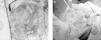

La tomografía computarizada (TC) realizada mostró una lesión de tejidos blandos que comprometía la hemimandíbula izquierda (fig. 2A y B). La biopsia de la lesión confirmó el diagnóstico de fibromixoma de origen odontogénico. Con este diagnóstico, se practicó resección completa macroscópica del tumor con reconstrucción con placa de mandíbula, por el servicio de cirugía plástica (fig. 3A y B).

Figura 3A y B. Procedimiento quirúrgico.